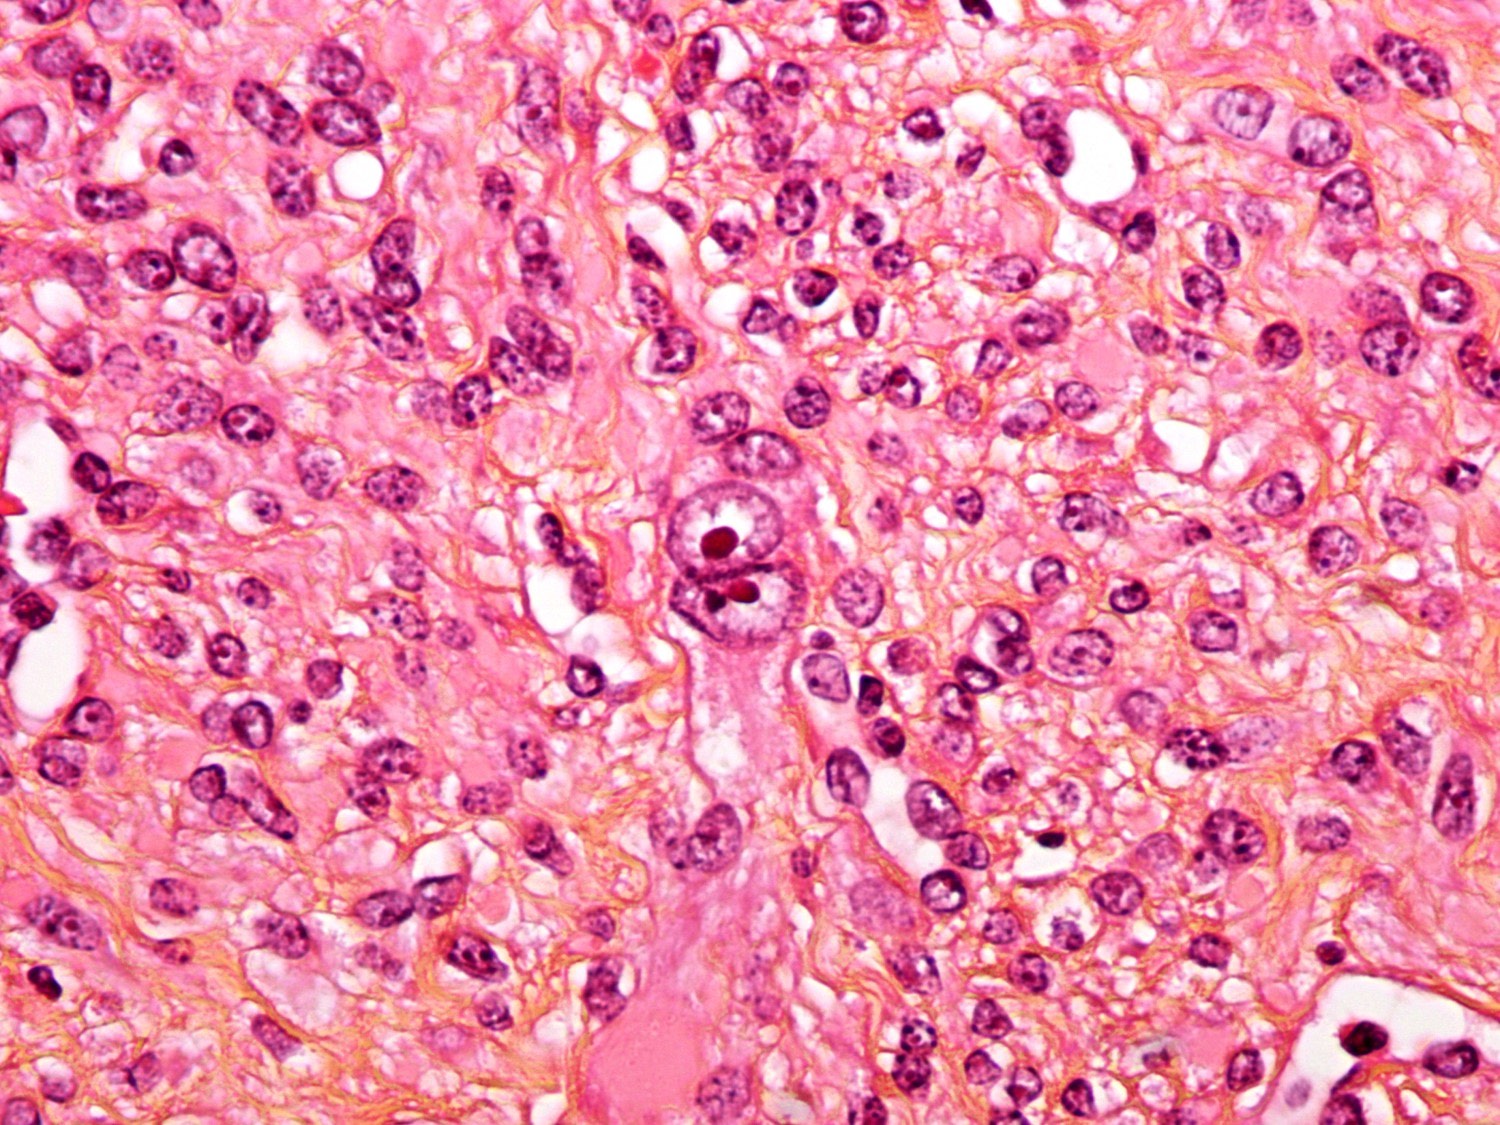

Webpathology.com: A Collection Of Surgical Pathology Images

leiomyosarcoma uterus myxoid pathology webpathology comments

Webpathology.com: A Collection Of Surgical Pathology Images

leiomyosarcoma uterus myxoid pathology webpathology stroma comments

Webpathology.com: A Collection Of Surgical Pathology Images

uterus leiomyosarcoma myxoid webpathology multinucleated